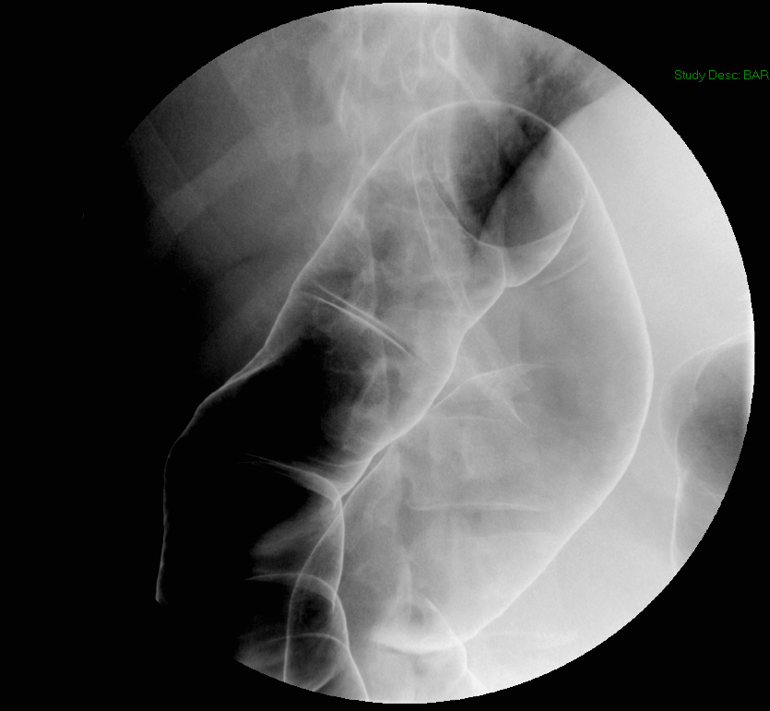

- After the patient begins drinking, obtain images of the upper and lower esophagus fully distended with barium:

(key image 1)

(key image 2).

- Have the patient turn to the right posterior oblique position.

- Repeat step 7 with the patient taking the cup of barium in their right hand:

(key image 3)

(key image 4)

(key image 5).